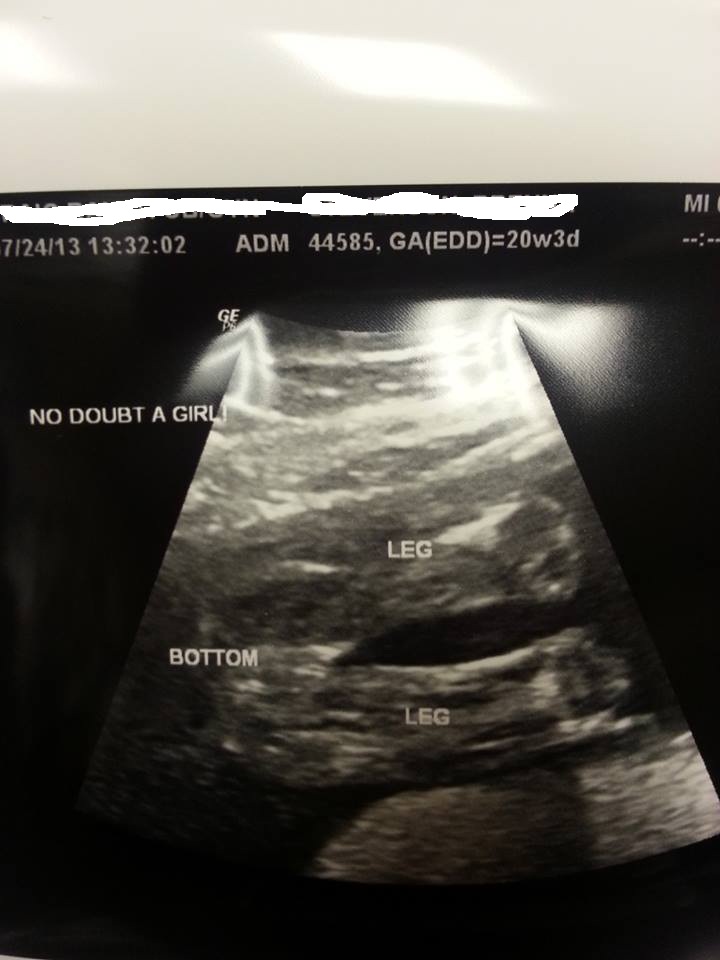

congratz, was this your 20 week scan or 16?

The top one is 16w 4d and the bottom is 20 weeks and 3 days